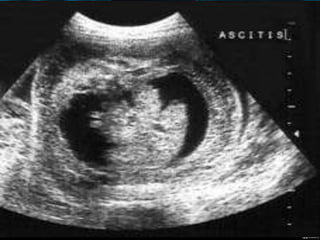

ASCITIS

•DESDE PEQUEÑAS COLECCIONES.

•ACUMULACIONES MAYORES.

PRESENCIA DE DOS O MÁS DE LOS

•ASCITIS FETAL

HALLAZGOS ECOGRÁFICOS: ASCITIS,

DERRAME PLEURAL, EDEMA SUBCUTÁNEO,